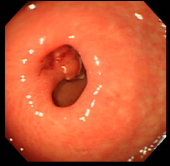

| 切除した部分をクリップで止血 | ポリープ切除した部分の1ヶ月後の粘膜 | ||